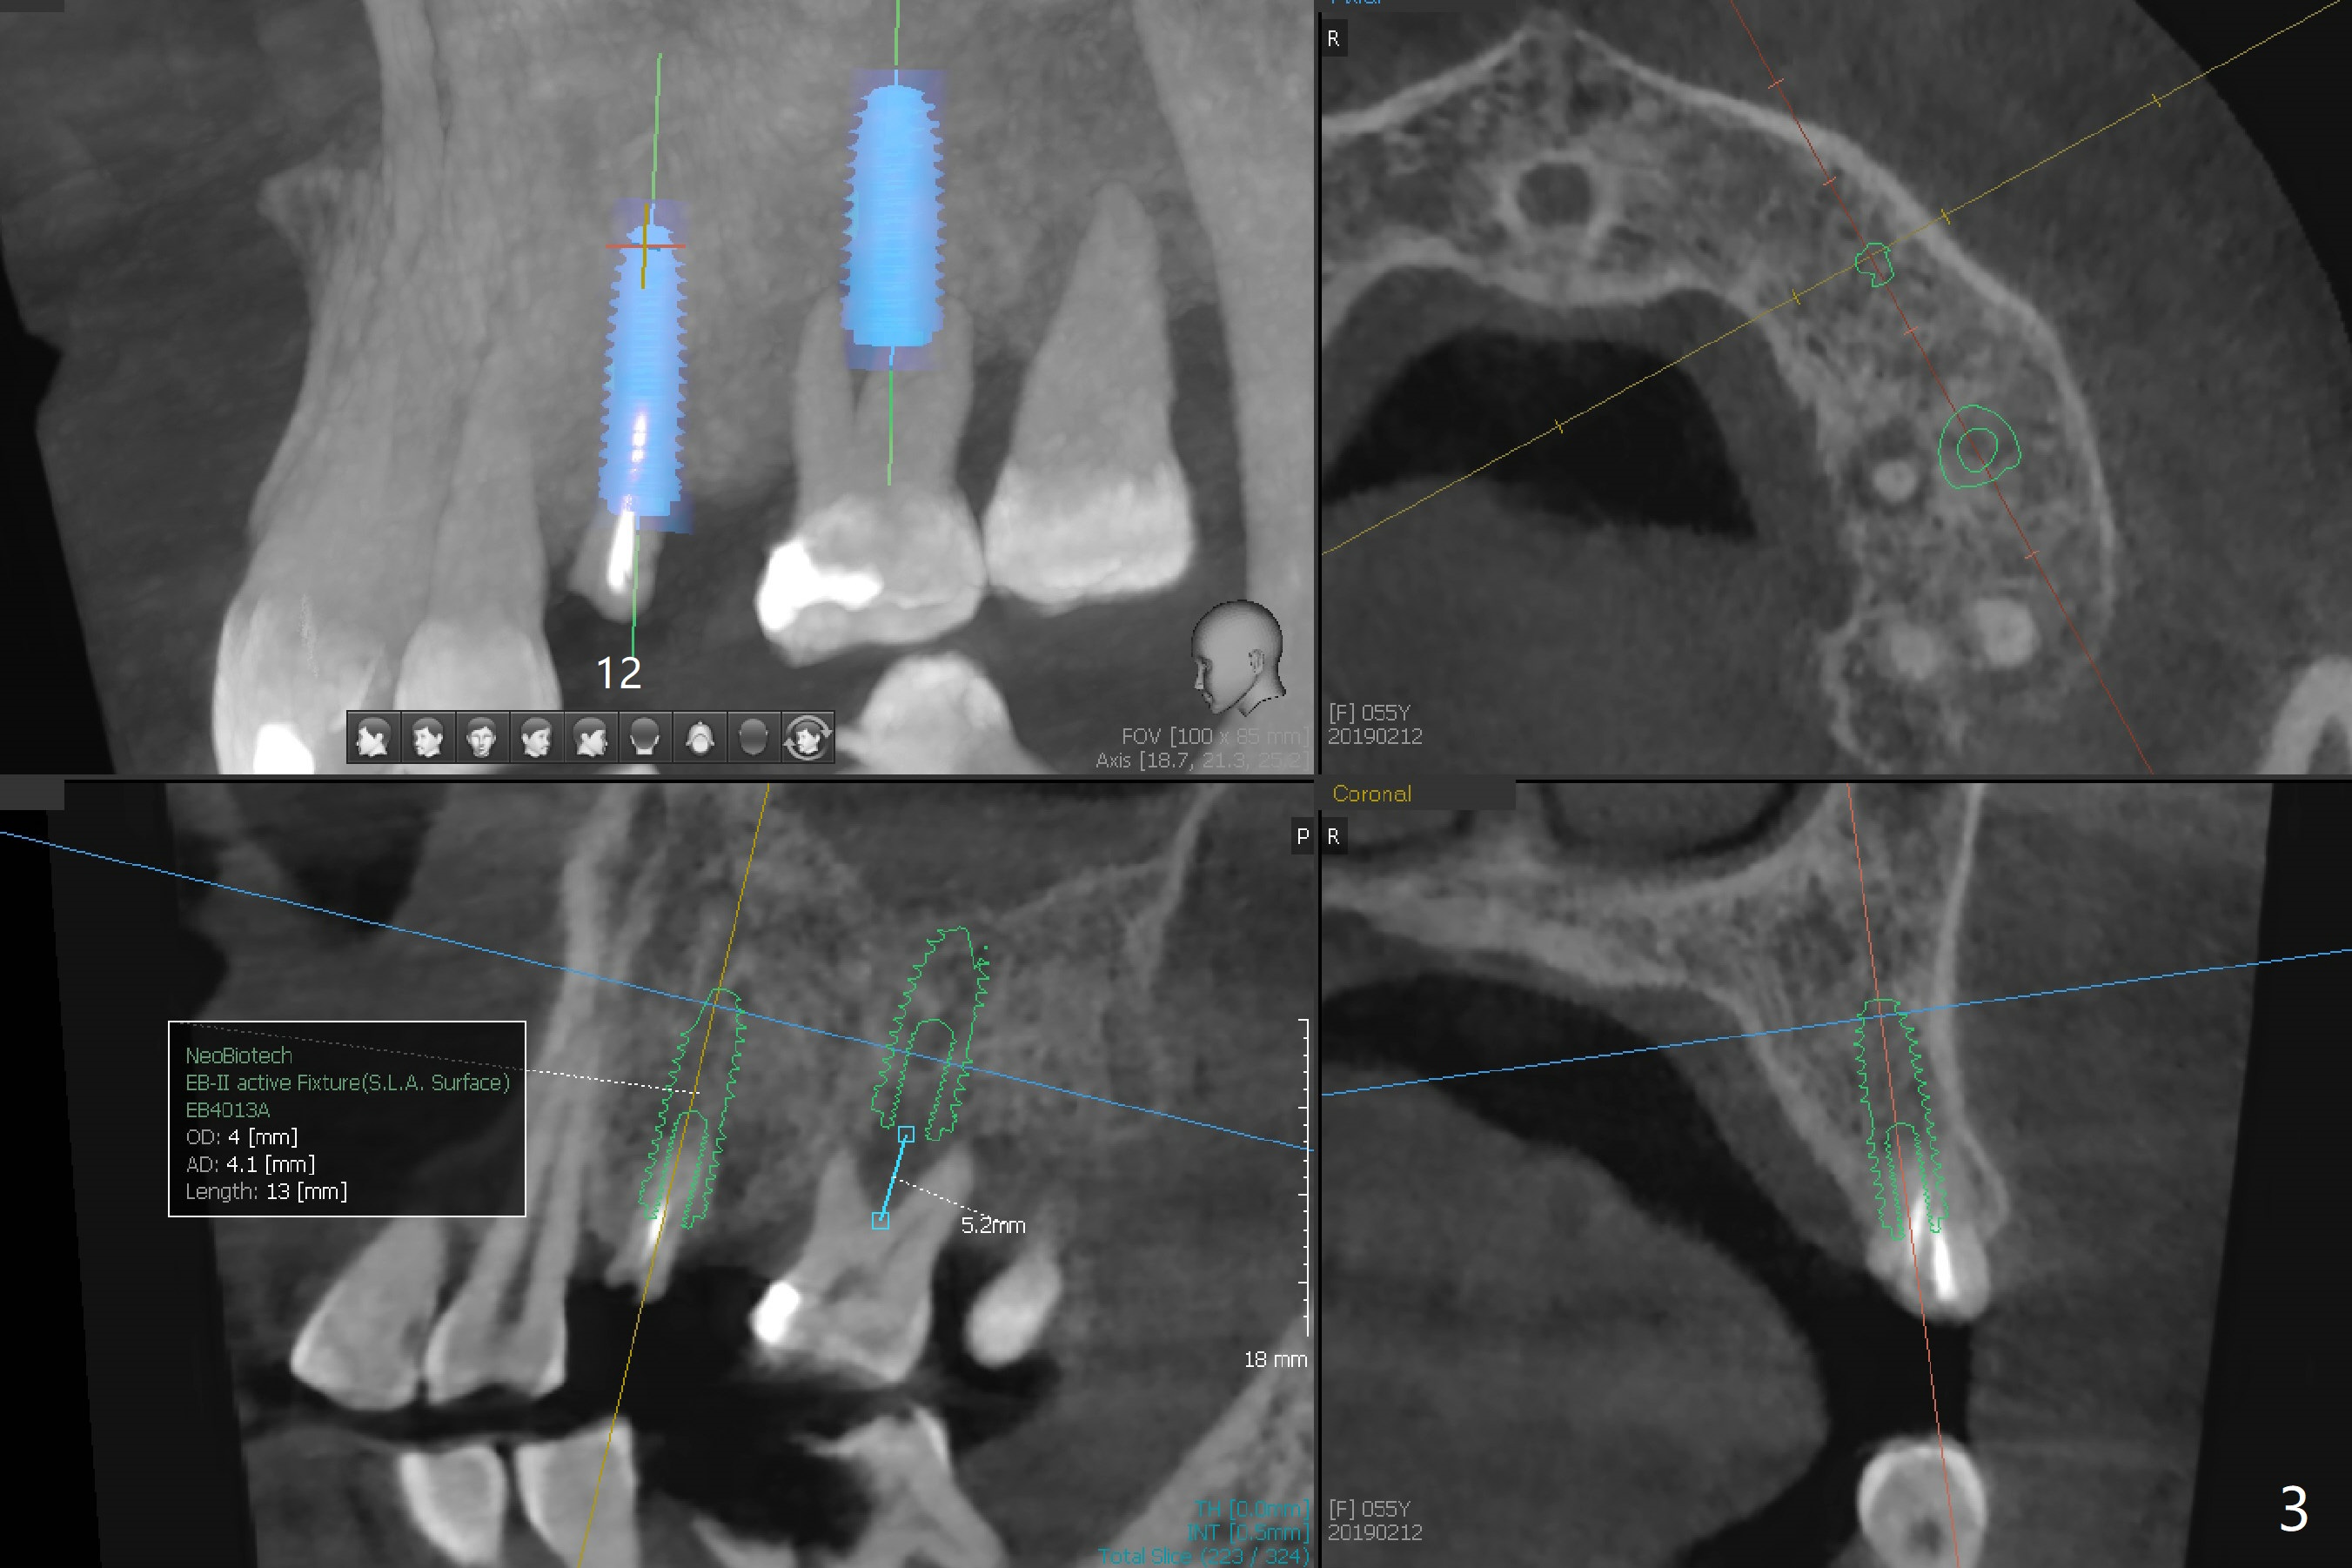

A 55-year-old woman has poor dentition, which is partially related to her previous history of ice chewing (Fig.1). The long bone height in the jaws suggests bruxism and requires as many teeth and implants as possible. After SRP, caries will be removed from #14 and 15 for determination of salvageability (Fig.2). The patient prefers to save the tooth #30. Endo referral will be recommended for #14 and 30. If the tooth #14 proves to be nonsalavageable, it will be extracted with #12 for immediate implants and subsequent FPD (Fig.3,4). Immediate implant will be avoided at #19 due to severe bone loss. Instead a short implant (5.5x5 or 6 mm) will be placed at #18, while a 4x11.5 mm one at #20 for FPD (Fig.5,6). All of the implant will use guides. There is a special point at #18. After use of 4.5 mm drill, the guide will be removed for free hand osteotomy using 5.0 mm drill, 5.5 mm tap and implant placement. PRF will be prepared for membrane and sticky bone at #19 and 20. For the lower right quadrant, treatment for #30 should be conducted first, either RCT or implant. The tooth #29 will be uprighted using #30 as an anchor, if the former is salvageable. The implant at #28 will be placed last (Fig.7,8).